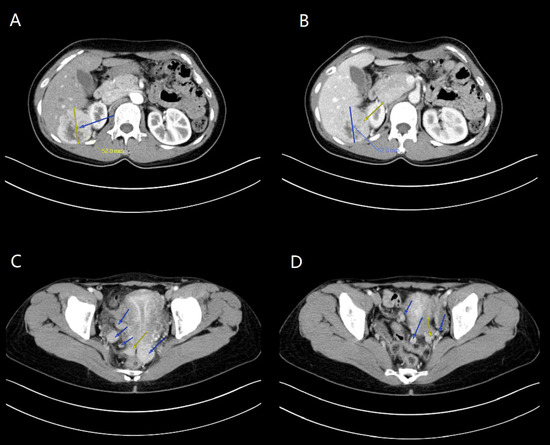

3.1.1. Case 1

3.1.2. Case 2

3.1.3. Case 3